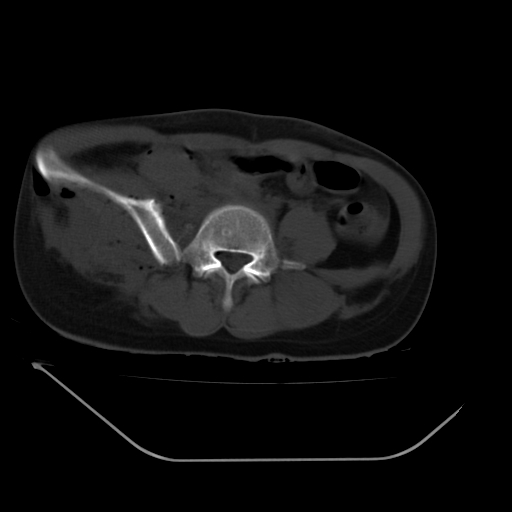

以下是引用liuyue在2008-7-19 13:02:00的发言:[br]1.肝右叶后下段及右肾挫裂伤伴腹腔积血。[br]2.右侧多发性肋骨骨折、横突骨折、右髂骨骨折伴周围软组织挫伤。[br]3.右侧腰大肌肿胀,并可见低密度影,如为气体,则肠道挫裂伤待除外。

以下是引用zhengfaming在2008-7-19 14:42:00的发言:[br]1.肝右叶后下段及右肾挫裂伤伴腹腔积血。脾脏挫裂伤待排[br]2.右侧多发性肋骨骨折、横突骨折、右髂骨骨折伴周围软组织挫伤。[br]3.右侧腰大肌肿胀,并可见低密度影,如为气体,则肠道挫裂伤待除外

以下是引用道哥在2008-7-19 16:52:00的发言:[br]肝右叶后下段及右肾挫裂伤、脾破裂伴腹腔积血。[br]2.双侧多发性肋骨骨折、横突骨折、右髂骨骨折伴周围软组织挫伤。[br]3.右侧腰大肌肿胀,并可见低密度影,如为气体,则肠道挫裂伤待除外。